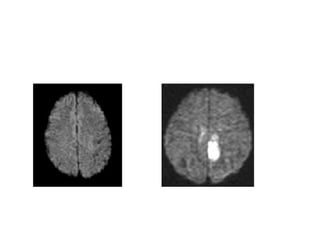

Diffusion Weighted Imaging (DWI)

• DWI is the most sensitive sequence for

stroke imaging.

DWI is sensitive to restriction of Brownian

motion of extracellular water due to

imbalance caused by cytotoxic edema.

Normally water protons have the ability to

diffuse extracellularly and loose signal.

High intensity on DWI indicates restriction

of the ability of water protons to diffuse

extracellularly.

This is why DWI is called 'the stroke

sequence'

DWI is the most sensitive sequence for stroke imaging.

DWI is sensitive to restriction of Brownian motion of

extracellular water due to imbalance caused by cytotoxic

edema.

Normally water protons have the ability to diffuse

extracellularly and loose signal.

High intensity on DWI indicates restriction of the ability of

water protons to diffuse extracellularly.

• Acute stroke causes excess intracellular water

accumulation or “cytotoxic edema”, with an overall

decreased rate of water molecular diffusion within

the affected tissue.

• Tissues with a higher rate of diffusion undergo a greater loss of

signal in a given period of time than do tissues with a lower

diffusion rate.

• Therefore, areas of cytotoxic edema, in which the motion of

water molecules is restricted, appear brighter on diffusion-

weighted images because of lesser signal losses.

• Hyperintense restriction from cytotoxic edema

• DWI improves hyperacute stroke detection to 95%

• High signal can persist up to 57 days post-ictus, (after 10

days, T2 effect may predominate over low ADC = "T2

shine-through")

• Corresponding low signal on ADC maps- May normalize

after tissue reperfusion, Note: Hyperintensity on ADC map

(T2 "shine-through") may mimic diffusion restriction

• Distinguishes cytotoxic from vasogenic edema in

complicated cases; especially helpful for evaluation of new

deficits following tumor-resection